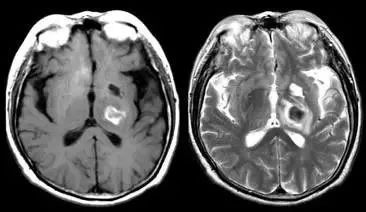

图片

脑出血亚急性晚期  T1 高信号(左),T2 高信号(右)